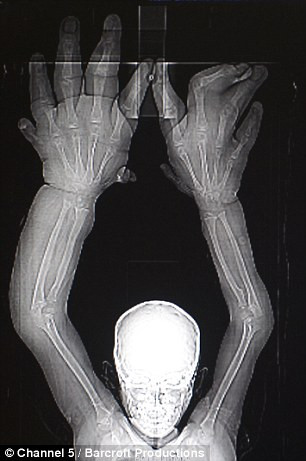

(Kiến Thức) -  Đôi bàn tay khổng lồ với hình dáng hết sức kỳ dị khiến cậu Mohammad Kaleem bị dân làng coi là quỷ dữ, là kẻ bị thần linh nguyền rủa.

Cậu bé Mohammad Kaleem, người Ấn Độ, năm nay 8 tuổi nhưng mắc phải căn bệnh hiếm gặp tạo ra đôi bàn tay khổng lồ. Cậu không thể tự ăn, mặc và thậm chí chẳng buộc được dây giày của mình.

Mỗi bàn tay của Kaleem nặng gần 13 kg và dài đến 13cm tính từ gốc bàn tay đến đầu ngón giữa.